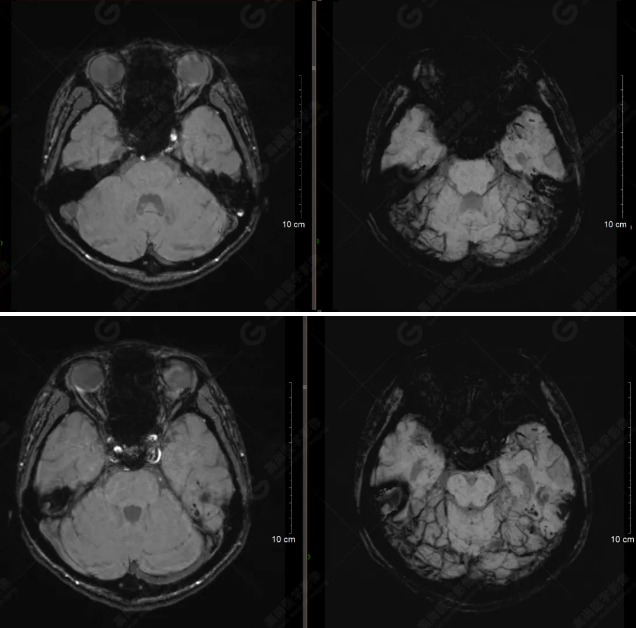

以下是平掃T2WI及FLAIR序列: